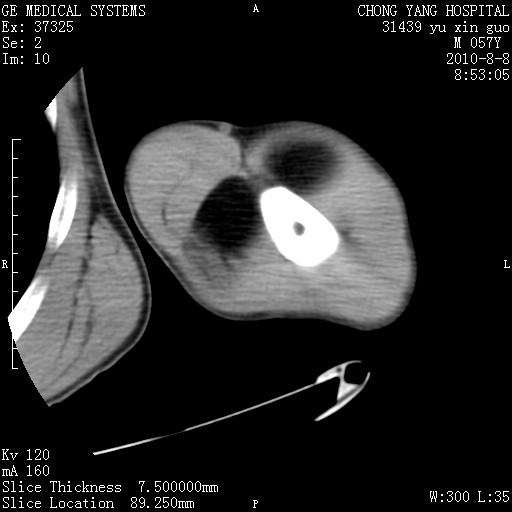

标题: CT28267:M57Y 上臂包块8年余。 [打印本页]

标题: CT28267:M57Y 上臂包块8年余。

包膜光滑、完整的脂肪密度肿块,支持脂肪瘤。